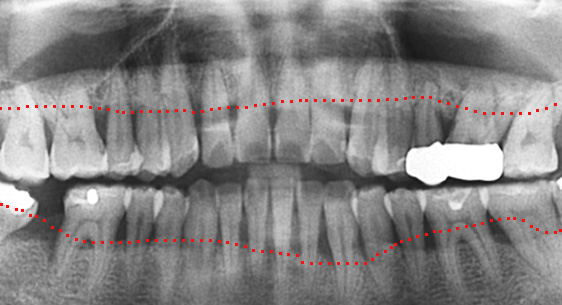

심한 염증으로 치조골이 광범위하게 소실, 아래쪽 신경관이 가까이 있어 치근단수술이 불가능한 상태, 타 병원에서 임플란트 진단을 받았지만,

고운미소치과에서 치아를 발치하고 뿌리 쪽 염증을 제거한 후 발치한 치아를 다시 심는 치아재식술을 시행하였습니다.

기존 신경치료 부위에 염증과 치조골이 소실되고 있는 상태

치아를 발치하고 염증을 제거, MTA로 충전하고 치아를 다시 심음. (난이도 최상)